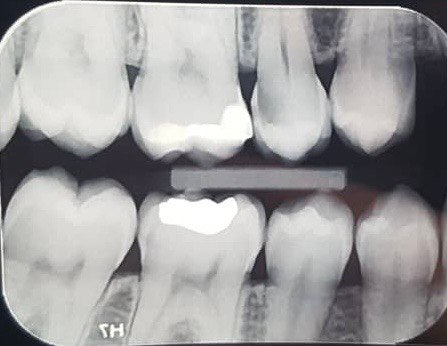

1. Which surfaces shows dental caries?

2. Which surface needs restoration?

4. Which surface needs restoration?

5. Which surface needs restoration?

8. Which surface needs restoration?